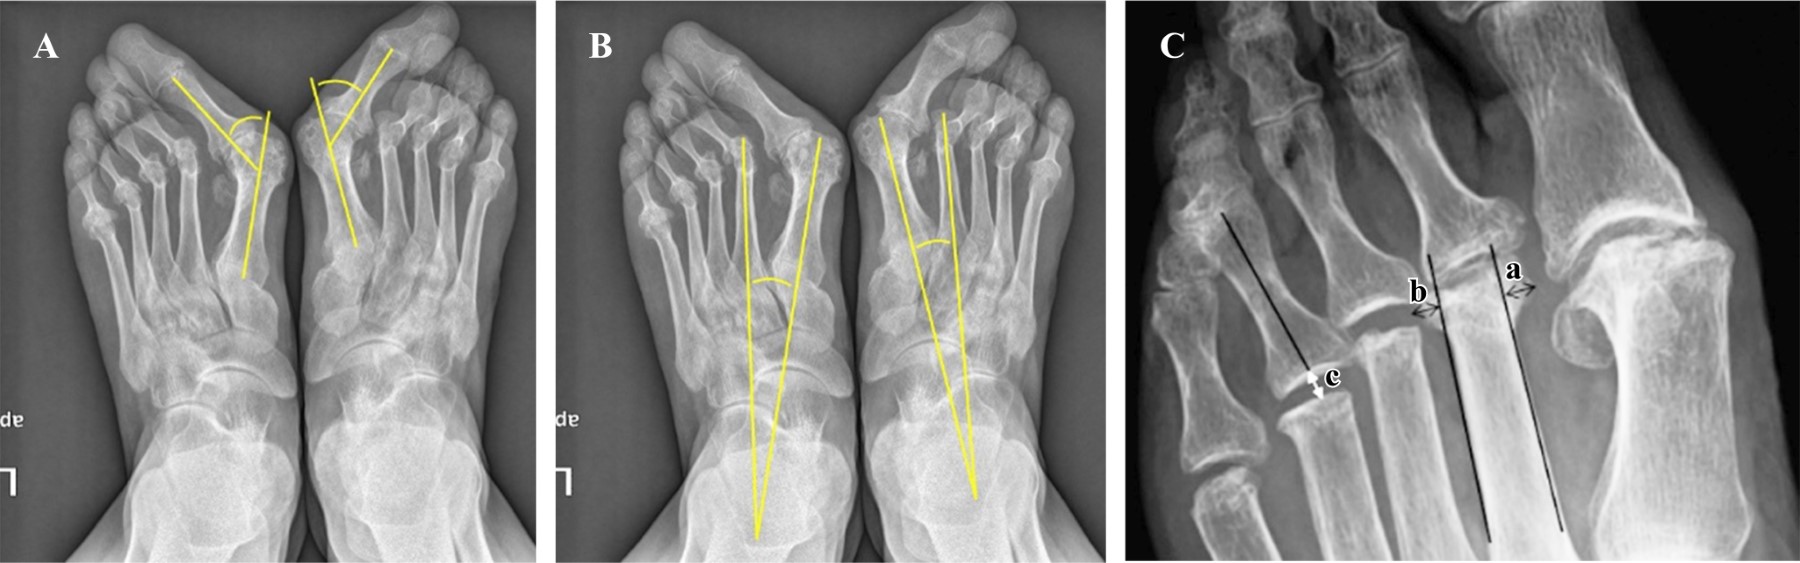

Evaluación radiográfica. Se realizó una evaluación de la luxación de la articulación MTF, el espacio de artroplastía de resección y el tamaño de los osteofitos por remodelación del muñón metatarsal. El espacio de artroplastía de resección se definió como la distancia mínima desde el punto de intersección entre el eje longitudinal y el extremo proximal de la falange proximal hasta el margen distal del muñón correspondiente del metatarsiano. El tamaño de los osteofitos se definió como la suma de la longitud de dos líneas perpendiculares desde el punto más prominente del osteofito hasta una línea tangencial a lo largo de la cortical medial y lateral del metatarsiano. La luxación de la articulación MTP y potenciales recurrencias se evaluaron antes de la cirugía, en el postoperatorio inmediato y en la última visita de seguimiento. El espacio de artroplastía de resección se evaluó en el postoperatorio inmediato y en la última visita de seguimiento. El ángulo intermetatarsiano (IMA) y el ángulo de hallux valgus (AHV) se evaluaron antes de la cirugía y después de la cirugía en la última visita de seguimiento. El tamaño de los osteofitos se midió en la última visita de seguimiento. Todas las medidas se basaron en radiografías anteroposteriores y laterales estándar de los pies en carga (Figura 1).

Desde el punto de vista radiográfico, el valor promedio del AHV en la última visita de seguimiento fue 21.4 ± 10.6 grados, significativamente más bajo que el valor medio preoperatorio de 49.7 ± 15.2 grados (p = 0.0001). El valor promedio de IMA también mejoró significativamente, desde 14.9 ± 3.6 grados preoperatorios a 8.4 ± 2.5 grados en promedio en la última visita de seguimiento (p = 0.001) (Figura 2).